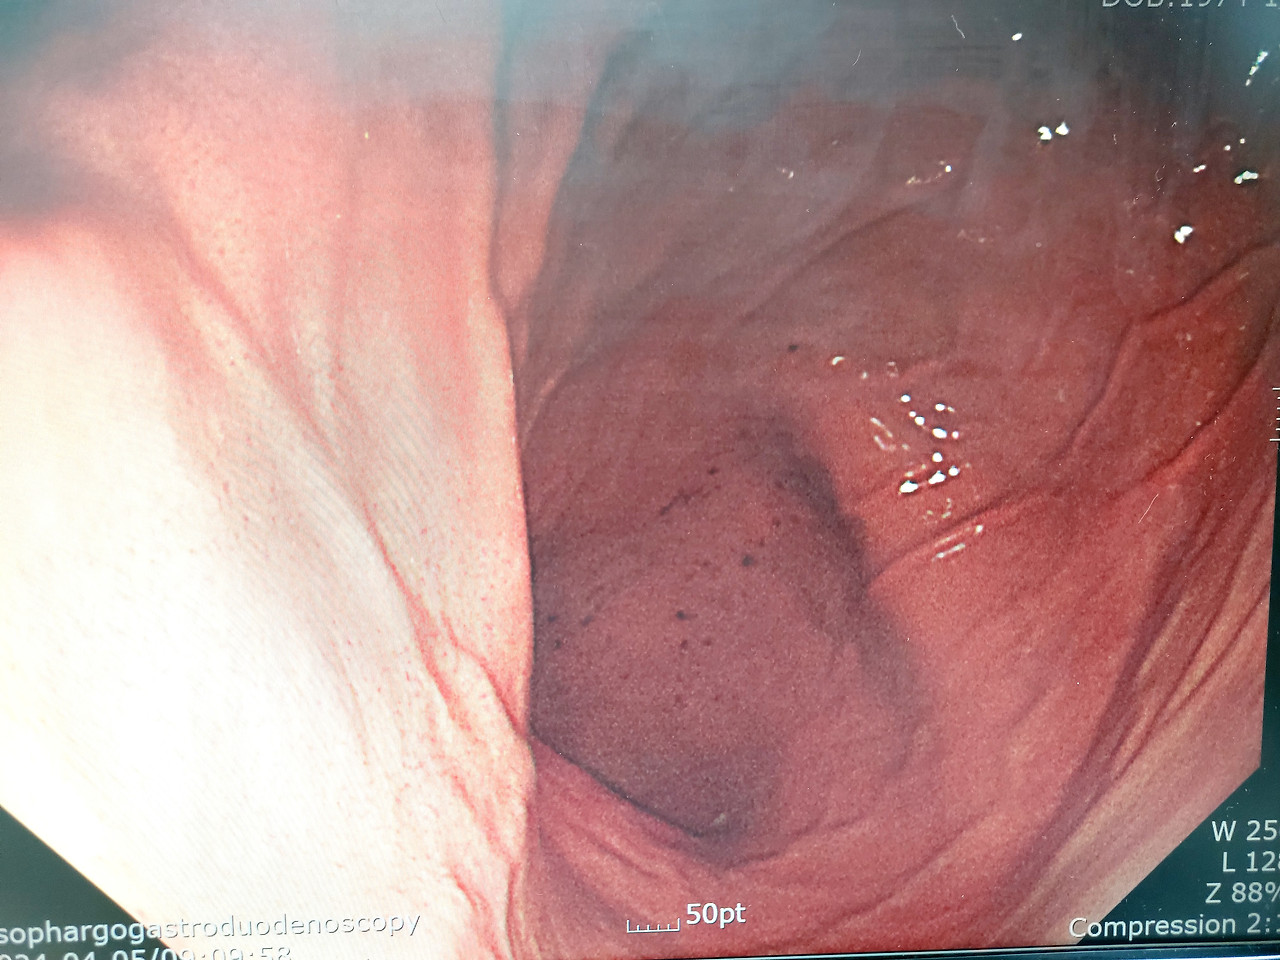

말리 비틀어진 나의 위와 출혈반점

4년 전에는 살 빼기 전이라 정말 나의 위장과 대장은 너무 반짝거렸다. 잘 씻겨져 오일을 발라 매끈거려 마치 아기 엉덩이 같이 통통하고 예뻤지만 살이 10kg 이상 빠졌으니 장기도 말라비틀어진 것이 아닌지 걱정이 되었다. 의사 선생님은 약간의 출혈이 있고 다른 이상 증상은 없다고 했다. 내가 너무 놀라 오라팡을 먹고 1리터 이상 토했지만 500ml 정도 토했다고 거짓말을 했다. 오라팡을 먹고 토하면 이런 경우가 가끔 있다고 했다. 다행이었다. 속이 아프면 약 처방을 내어 주겠다고 했지만 나는 아무렇지도 않아서 약 처방을 받지 않았다. 의사 선생님은 사진을 찍고 싶다고 하니 휴대폰을 건네받아 사진을 직접 찍어 주었다. 어쨌거나 검사는 다 했고 위와 대장도 별 이상이 없었다. 지하철을 타고 집으로 돌아와 죽을 먹고 뜨끈한 전기장판을 틀고 잠을 잤다. 눈을 뜨니 4시간 정도 지나 저녁이 되었다. 그때부터 속이 아파오기 시작했다. 뜨끈한 미역국을 먹고 일찍 잠이 들었다. 검사결과는 일주일 후 문자로 연락을 준다고 했다.

다음날 출혈이 있는 나의 위 사진을 들여다봤다. 4년 전 내가 봤던 모습이 아니었다. 너무 말라 있었다. 지쳐서 식욕은 없어도 아이들 밥은 해줘야 하고 청소며 빨래도 해야 했다. 바쁘게 움직이다 보니 아무것도 먹지 않은 게 생각났다. 뭐라도 속을 채우자 싶어 억지로 조금씩 먹었지만 체중이 올라가지 않았다. 건강검진을 마치고 집으로 돌아왔을 때 빈속인 나는 겨우 41kg을 넘겼다. 굶지 않고 있지만 그렇다고 많이 먹지도 않아서 주말에는 김밥도 싸 먹고 애정하는 고구마도 삶아 먹었다. 나이가 드니 먹는 것도 힘이 든다. 그렇게 먹었는데 45kg이 되지 않아 노력대비 헛수고를 했다.